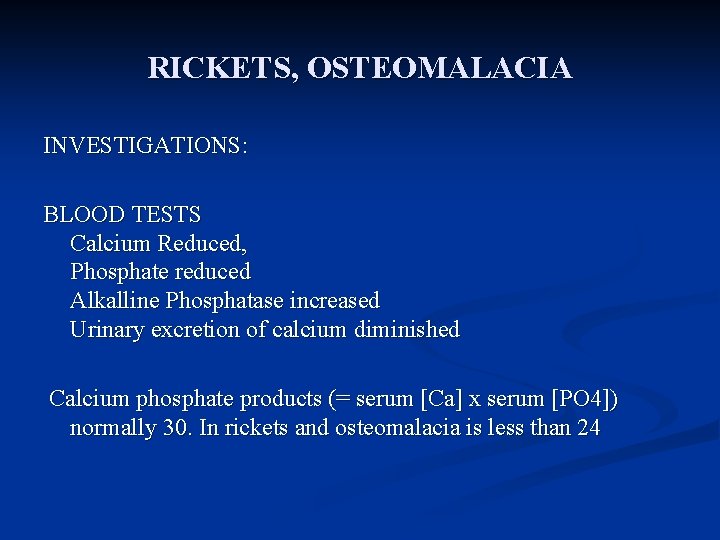

RICKETS, OSTEOMALACIA INVESTIGATIONS: BLOOD TESTS Calcium Reduced, Phosphate reduced Alkalline Phosphatase increased Urinary excretion of calcium diminished Calcium phosphate products (= serum [Ca] x serum [PO 4]) normally 30. In rickets and osteomalacia is less than 24

Osteomalacia & Rickets Diagnosis n Other laboratory abnormalities may include Hypocalcemia n Hypophosphatemia n Elevated serum alkaline phosphatase n

Biochemical findings in rickets n Alkaline phosphatase usually is ↑in all forms of rickets. n Serum phosphorus concentrations usually are↓ in both hypocalcemic and hypophosphatemic rickets. n Serum Ca is ↓only in hypocalcemic rickets. n Serum parathyroid hormone typically is ↑in hypocalcemic rickets, in contrast it is N in hypophosphatemic rickets. n 25 -OH vitamin D reflect the amount of vitamin D stored in the body, and is ↓in vit D deficiency. n 1, 25 -OH 2 vitamin D can be↓, N or ↑in hypocalcemic rickets and usually is N or slightly ↑in hypophosphatemic rickets.

Laboratory findings in Osteomalacia Decreased serum calcium levels n Decreased serum phosphorus levels n Elevated serum alkaline phosphatase n Xrays show bone demineralization n

Laboratory findings in Osteomalacia Decreased serum calcium levels n Decreased serum phosphorus levels n Elevated serum alkaline phosphatase n Xrays show bone demineralization n